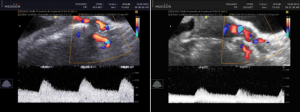

Doppler Obstétrico Feto-Placentario

Doppler Obstétrico Feto-Placentario Evalúa en forma no invasiva el flujo de los vasos sanguíneos de la placenta, del feto, útero y del cordón umbilical, determina cómo